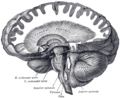

| Figure 1b: MRI image showing a mid- sagittal view of the human brain, with the cerebellum in purple. | ||

The cerebellum is located in the inferior posterior portion of the head (the hindbrain), directly dorsal to the pons, and inferior to the occipital lobe (Figs. 1 and 3). Because of its large number of tiny granule cells, the cerebellum contains more than 50% of all neurons in the brain, but it only takes up 10% of total brain volume. The cerebellum receives nearly 200 million input fibers; in contrast, the optic nerve is composed of a mere one million fibers.